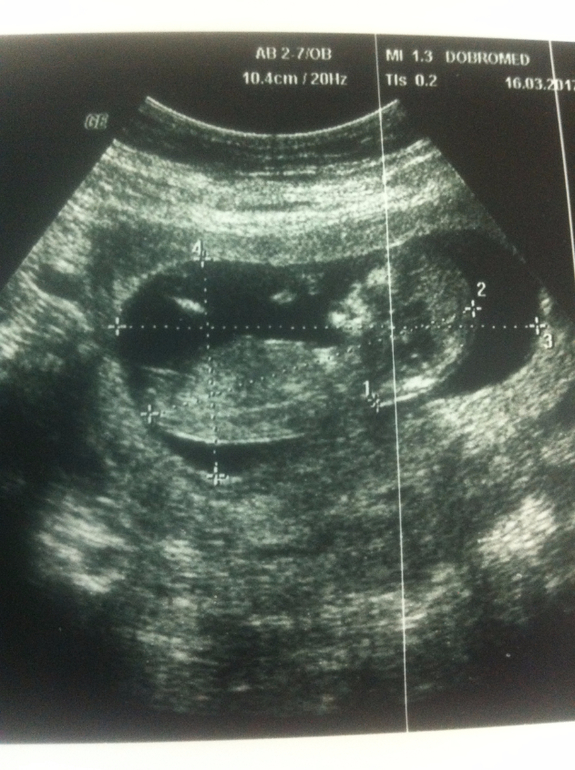

1-ый скрининг пройден)))

Результаты: УЗИ, КТГ, доплера, скринингаПо месячным срок 11 недель 3 дня

по моему календарю 11 недель 7 дней

по УЗИ 12 недель 6 дней

По УЗИ-скринингу всё у нас хорошо. Лапуля наша активно двигается, машет ручкой, зевает))) КТР - 5,8 см, а полная длина плода приблизительно 9 см.

Средний диаметр плодного яйца 5,4 см

КТР 5,8 см

Толщина воротниковой зоны 1,2 мм

Аномалии плода не выявлены

Хорион по задней стенке матки. Толщина 1,7 см

Пуповина визуализируется

Желточный мешок без видимой патологии д=0,5 см

Длина шейки матки 4,2 см внутренний зев сомкнут

БПР= 18,4

ЛЗР= 25,2

ОГ= 69,6 мм

Патологий со стороны плода не выявлено